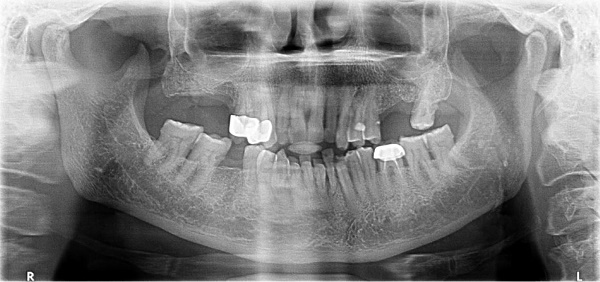

The Orthopantomography (OPG) showed no evidence of bone involvement. The initial working diagnosis was pyogenic granuloma though the suspicion of recurrence of ameloblastoma was not ruled out (Figure 2).